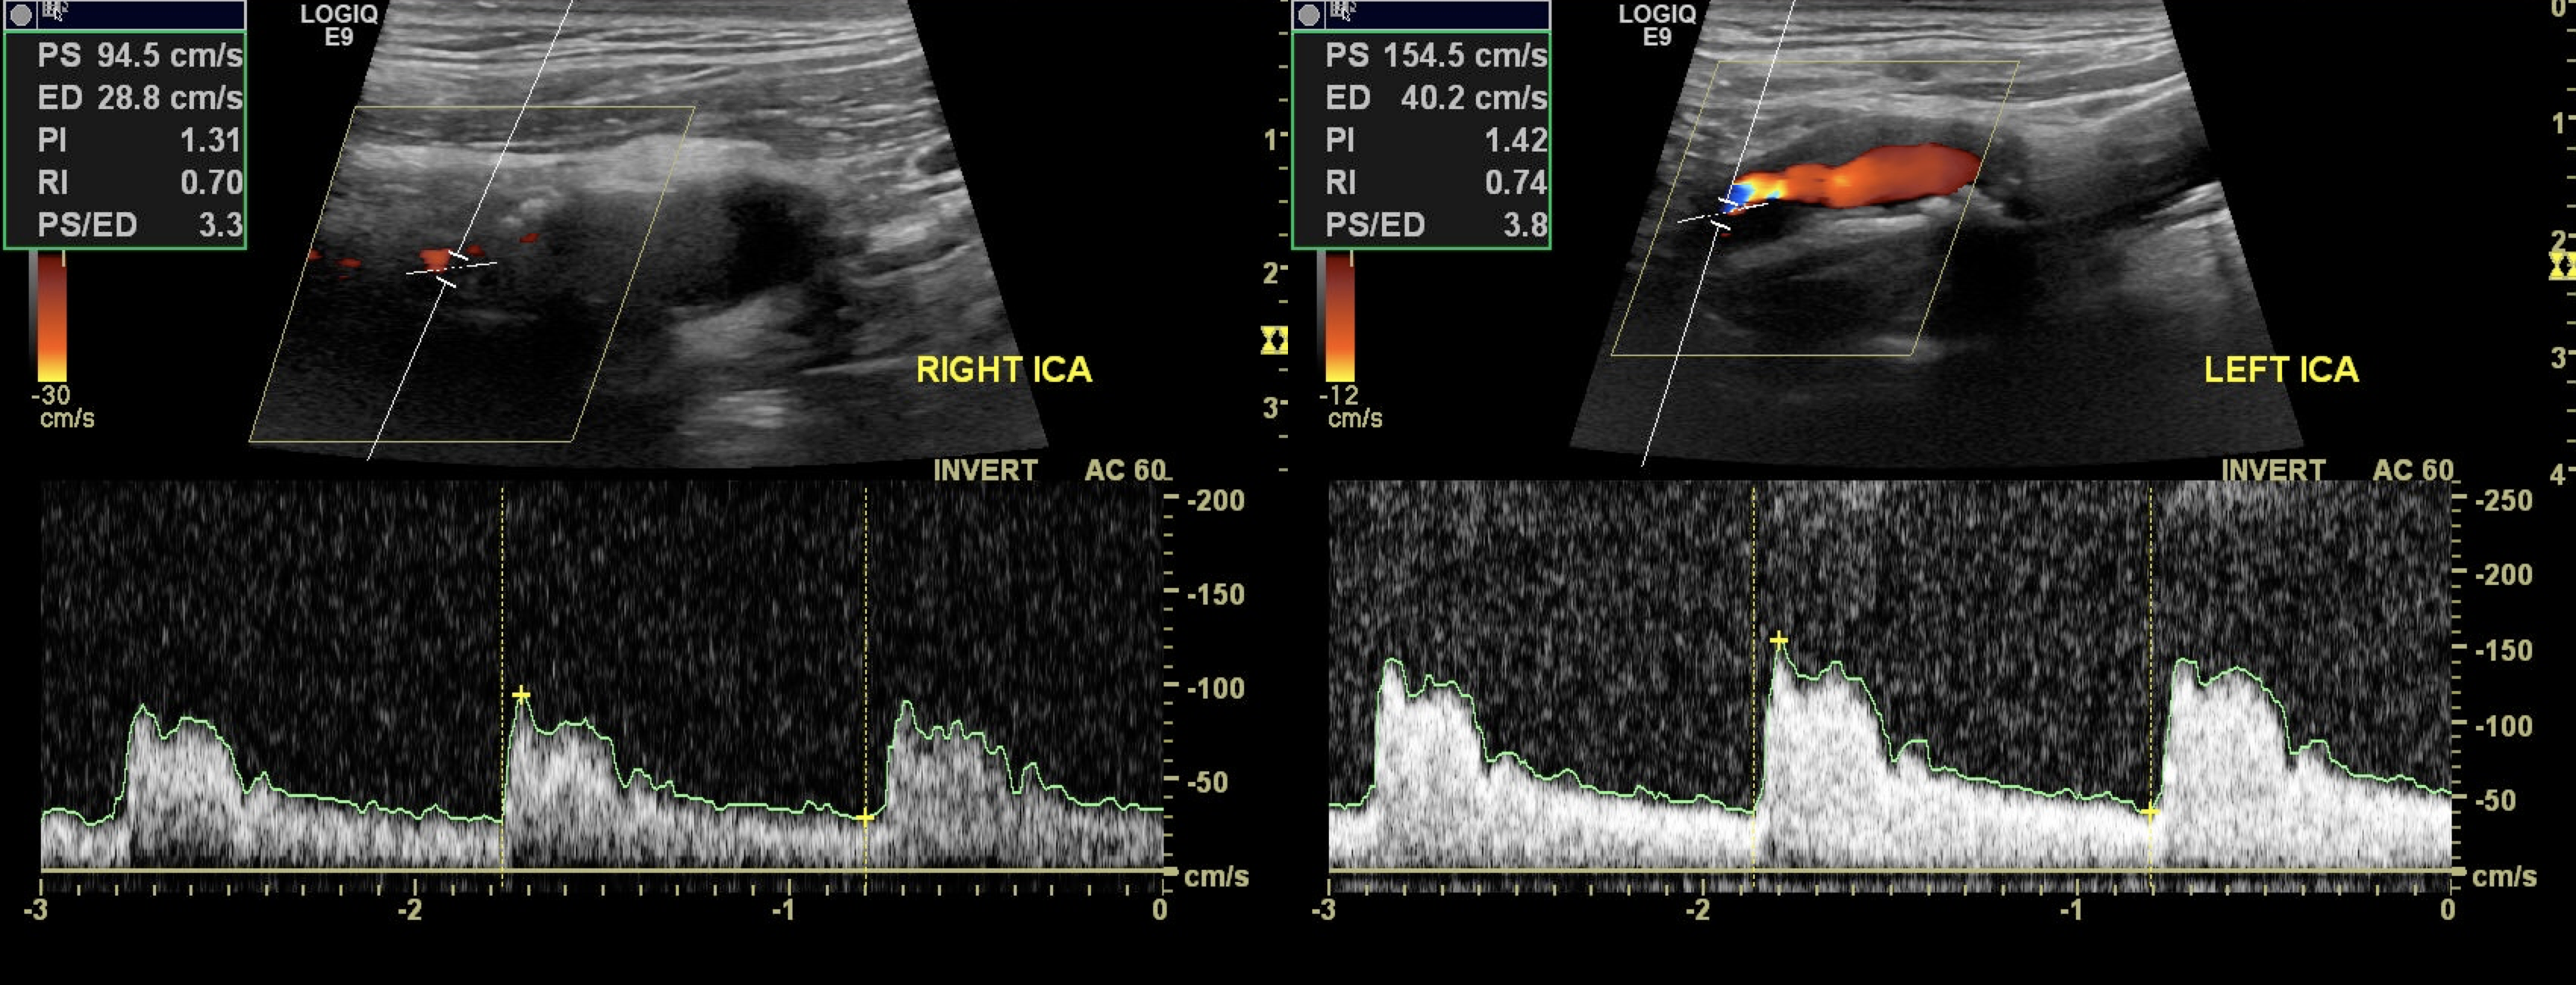

좌측 척추동맥과 양측 내경동맥의 협착이 확인된 자기공명 혈관조영검사(magnetic resonance angiography, MRA)

좌측 근위부 내경동맥의 중등도 협착(60–69%) 및 우측의 경도 협착이 관찰된 경동맥 초음파 검사